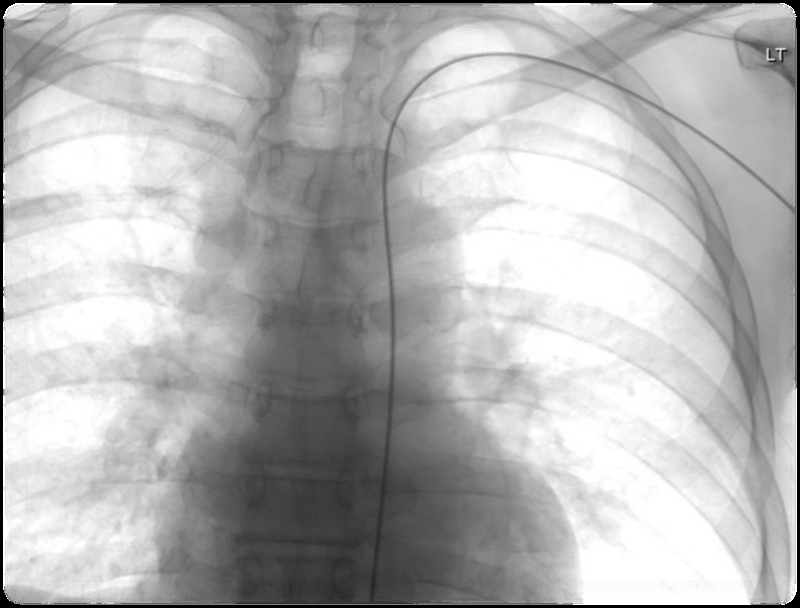

术中,游科医师取患者左侧桡动脉入路,在局部麻醉后穿刺,置入血管鞘,用导管配合超滑导丝分别插管至腹腔干、肝总动脉行血管造影检查,发现肿瘤病变滋养动脉源于肝左动脉及其分支,再用微导管在微导丝引导下插管至左肝动脉分支,对3支肿瘤滋养动脉插管,并用药栓塞肿瘤血供。

不管是经股动脉,还是经桡动脉肝癌介入手术,这两种手术方式一样,都是通过导管到达肝脏上的肿瘤血管,通过化疗栓塞肿瘤,从而达到治疗目的。不同的是,两者选择的入路方式不一样:经桡动脉,是从手腕的桡动脉进行手术;经股动脉,是从大腿根部的股动脉插入导管进行手术。

而经桡动脉肝癌介入手术的最大优点在于,患者的舒适度更高,并发症更少,住院时间短等。因该手术一般选择从左侧桡动脉入路,导管到达肝脏血管的距离更短,避开了头臂干及,非优势手等因素,患者术后不需要卧床,可以下床活动,也不会发生尿储留、血栓这些并发症。虽然左手活动会受限,但只有2-4小时的压迫止血时间。一般术后第二天复查后没有相应并发症即可出院。